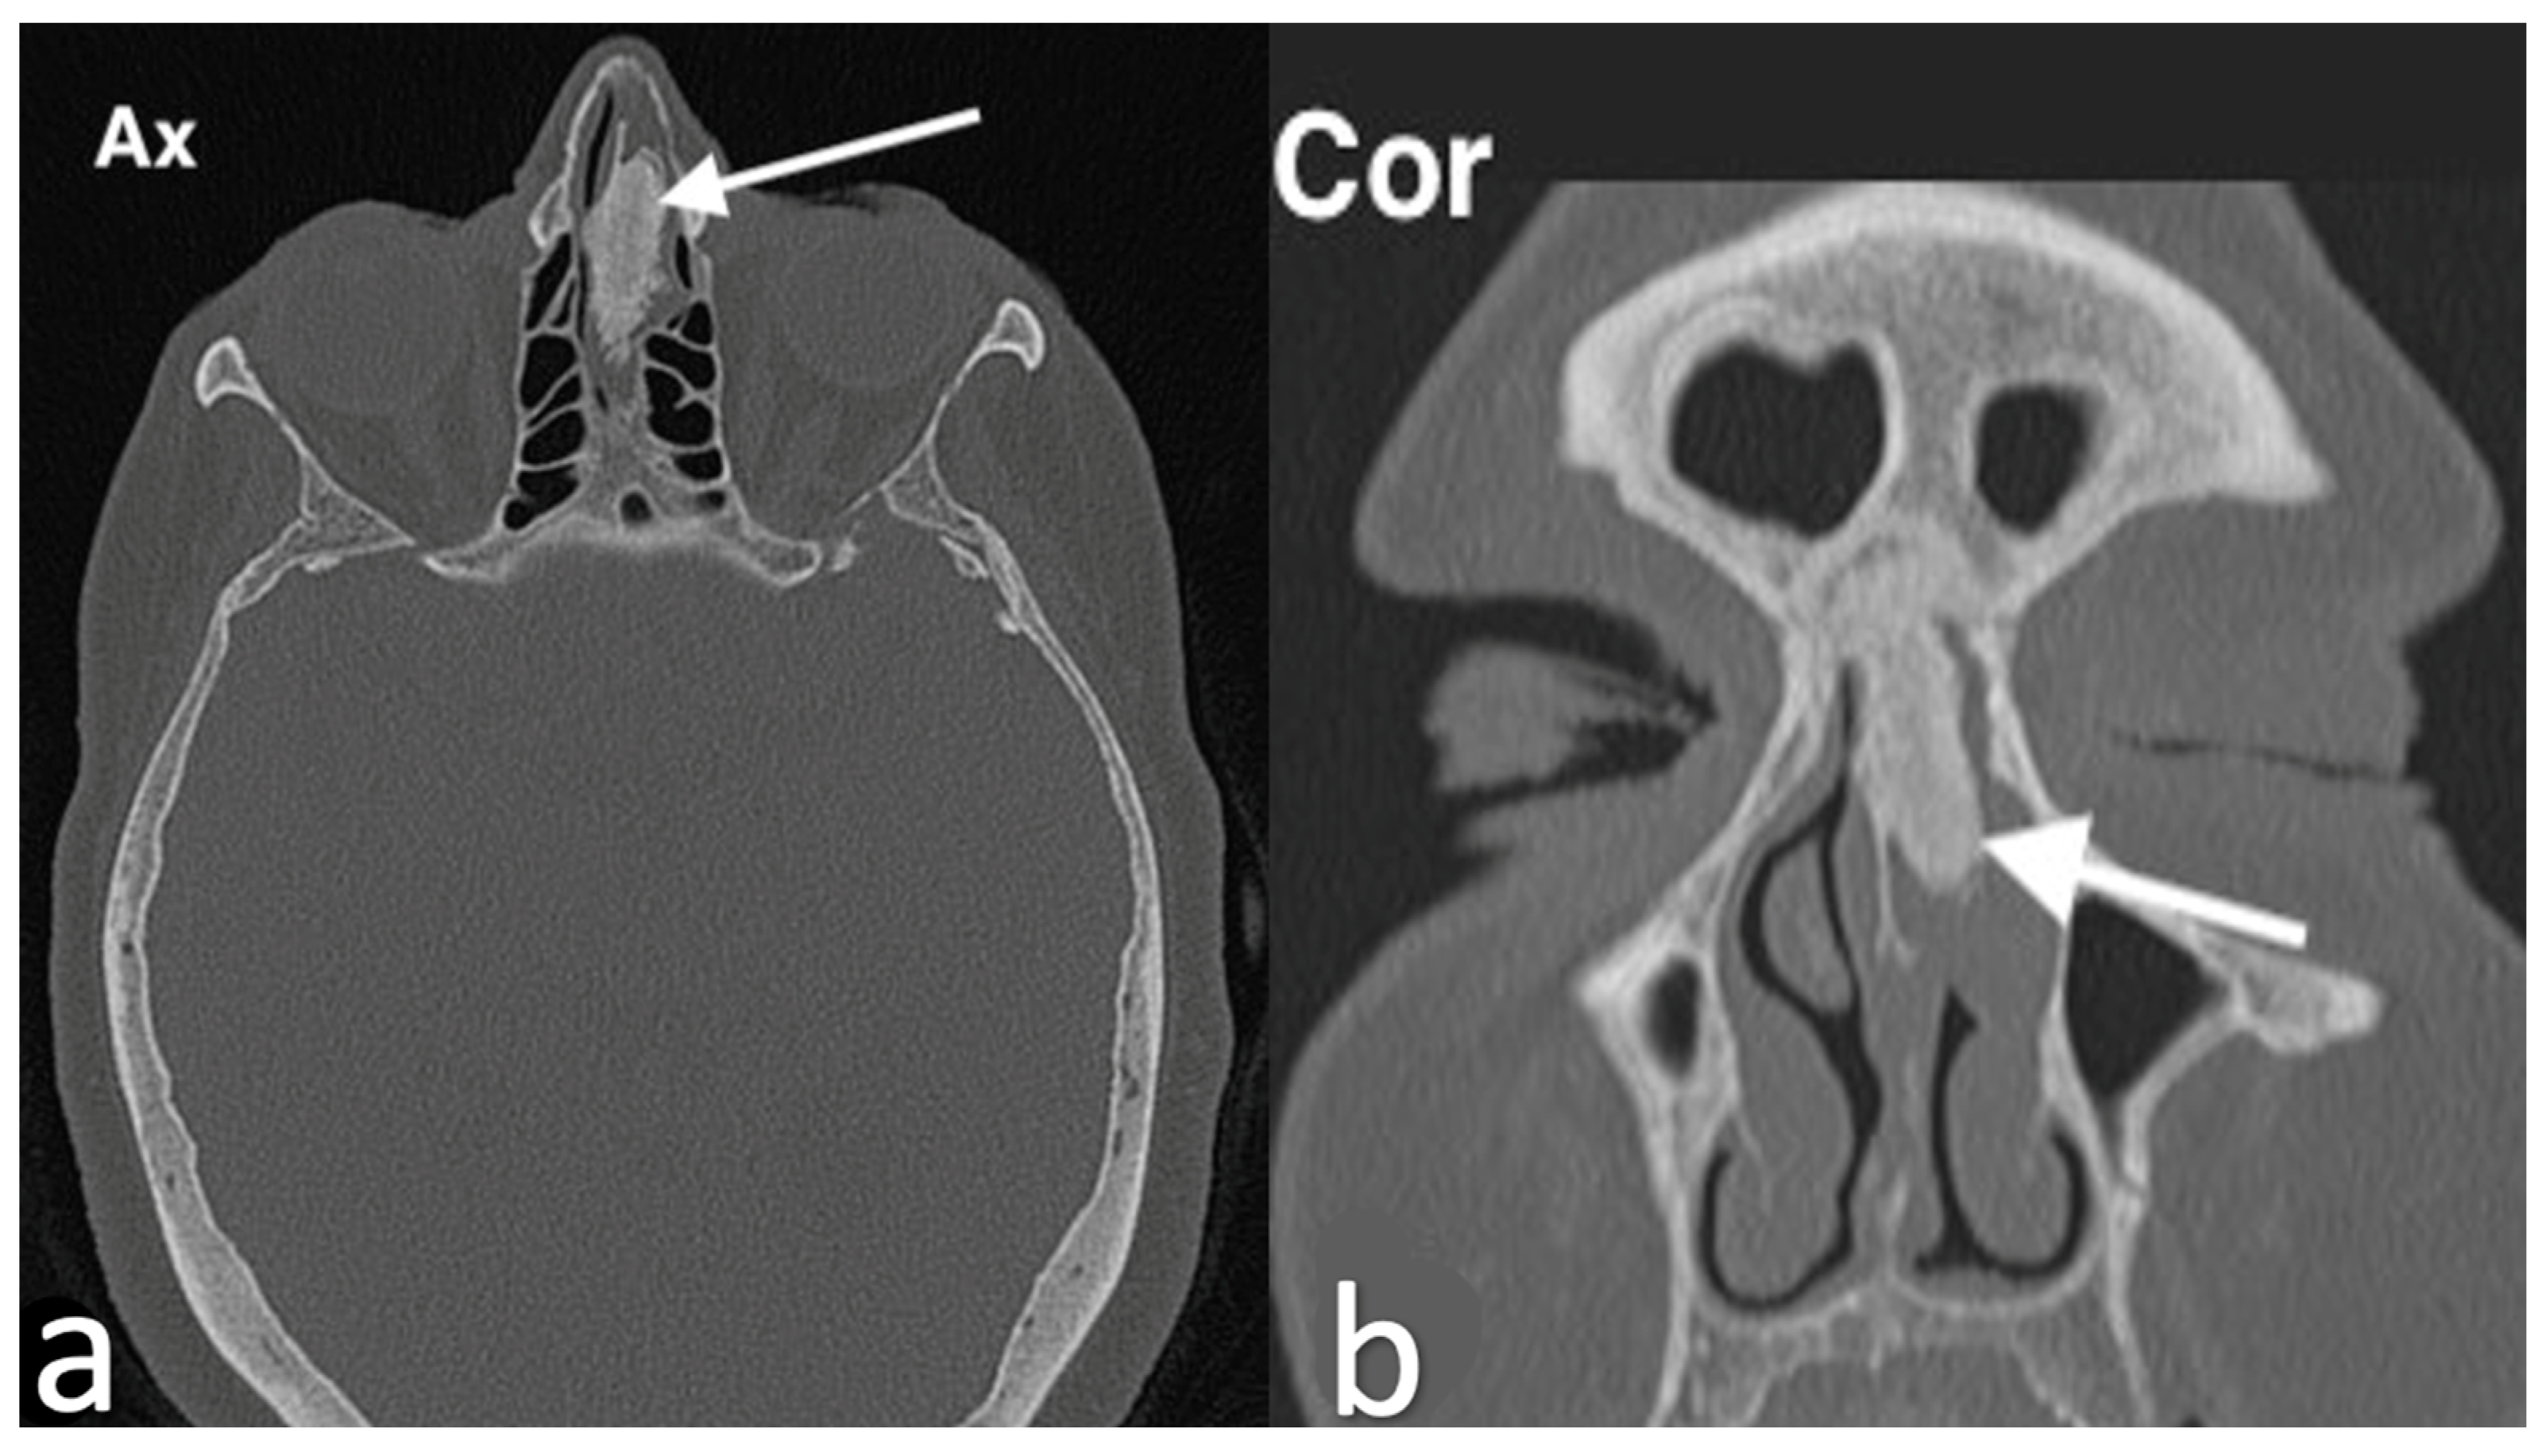

3.1.3. Inverted Mesiodens